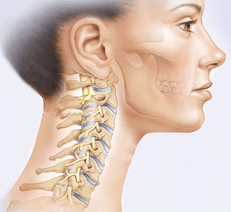

Остеохондроз шийного відділу є найнебезпечнішим видом захворювання. Шийний відділ хребта складається з семи дисків і є найбільш рухомим відділом хребта, який забезпечує можливість нахилів і поворотів голови. Має відносно слабкий м'язовий корсет. У той же час нестабільність шийного відділу хребта в поєднанні з постійними фізичними навантаженнями (необхідність підтримувати голову, контролювати повороти і нахили) пояснюють високу схильність цього відділу хребта як до травм, так і до дегенеративних змін, якими, по суті, є остеохондроз.

Невеликий шийний відділ містить багато нервових каналів і кровоносних судин, які живлять мозок. У шийному відділі хребці більш щільно прилягають один до одного. Тому навіть с

Невелика зміна в одному з хребців викликає здавлення або зміщення нервів і кровоносних судин.

Невелика зміна в одному з хребців викликає здавлення або зміщення нервів і кровоносних судин.Через порушення мозкового кровообігу виникають мігрені, вегето-судинна дистонія та гіпертонія, проблеми з серцево-судинною та дихальною системами, слухом, зором, координацією. У запущеній формі шийний остеохондроз може призвести до синдрому хребетної артерії. Хребтова артерія кровопостачає довгастий мозок і мозочок. При здавленні артерії може розвинутися ішемія головного і спинного мозку, виникнути спінальний інсульт.